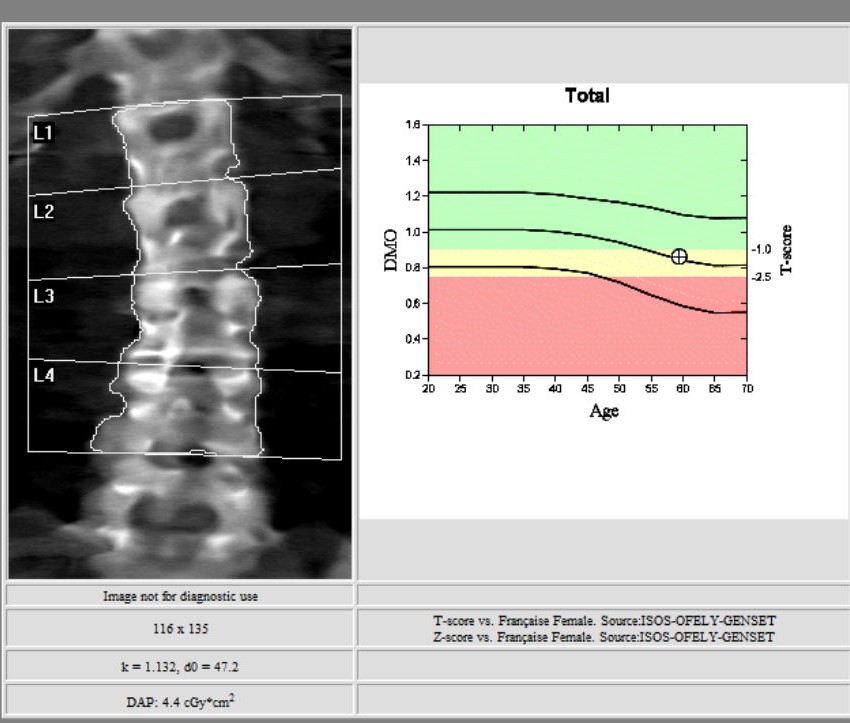

L’ostéodensitométrie mesure précisément la densité osseuse au niveau de deux sites principaux (souvent le rachis lombaire et le col fémoral), grâce à une technique dite biphotonique utilisant deux faisceaux de rayons X à très faible dose.

Elle constitue aujourd’hui la méthode la plus précise et la plus fiable pour diagnostiquer l’ostéoporose et évaluer le risque de fracture.

1. le rachis lombaire ;